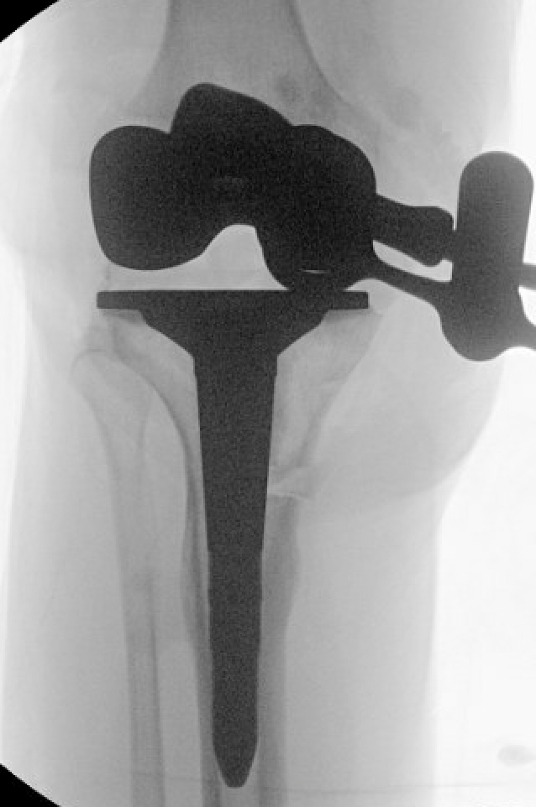

Trial components were inserted and demonstrated balanced flexion and extension gaps and central patellar tracking without the need for lateral release. The tibia was subsequently punched after confirming appropriate rotation for adequate patellar tracking. Final implantation proceeded with pressurized cement for the posterior-stabilized femoral component and the tibial baseplate under tourniquet insufflation. The diaphyseal press-fit stem was again confirmed to span the osteotomy by more than two cortical diameters under fluoroscopic guidance (Figure 4). Autogenous cancellous graft harvested from the femoral chamfer cuts was tightly packed into the osteotomy gap and along the medial cortex. The patella was resurfaced with a medialized polyethylene button.

The two TTO cortical screws were removed. Attention then turned to the extra-articular deformity. Under biplanar fluoroscopic control an oblique medial open-wedge osteotomy was created six centimeters distal to the tibial plateau at the apex of the varus malunion (Figure 3). A laminar spreader was gently inserted and opened until a neutral mechanical hip–knee–ankle axis was achieved, as confirmed with an extramedullary alignment rod extending from the center of the femoral head to the center of the ankle mortise.

A surgical assistant steadied the correction by holding laminar spreader and distal leg during tibial preparation. The tibial canal was sequentially reamed to accommodate a 15-mm diameter, 150-mm press-fit stem. Standard measured-resection technique was used on the femur with an intramedullary guide set to 6˚ of valgus. Femoral rotation was set to 4˚ of external rotation relative to the posterior condylar axis and parallel to the trans epicondylar axis—an amount chosen to optimize patellar tracking without over-stuffing the lateral compartment. The tibial proximal cut was made perpendicular to the mechanical axis with a targeted posterior slope of 3˚. Initial tibial component rotation was referenced to the medial one-third of the tibial tubercle and patellar tendon trajectory.